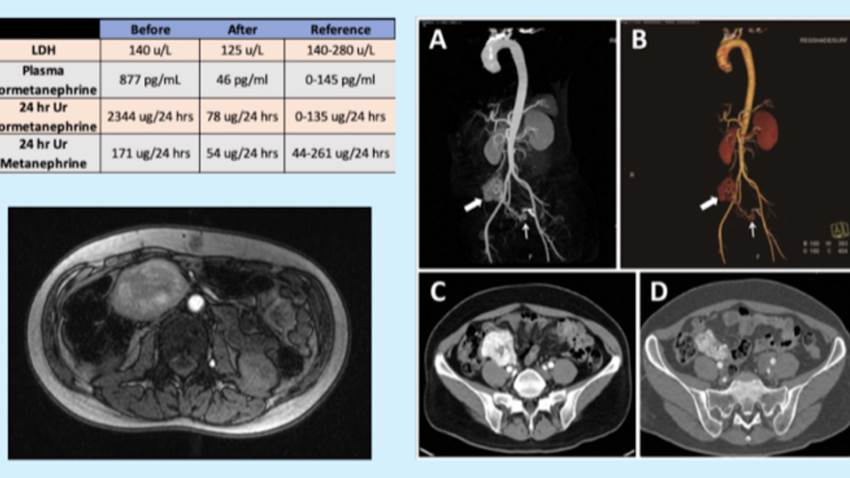

Médicos descubren tumor en zona lumbar de paciente puertorriqueño debido a fuertes dolores

El dolor de espalda en la zona lumbar pudiera ser común hoy día, debido a lastimaduras del área baja de la misma por distintas razones físicas y clíni...